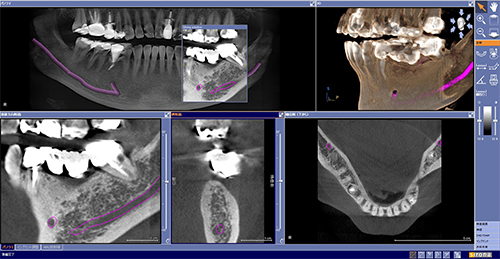

![]() インプラントの治療には正確な距離計測が必要となります。 CT撮影により正確な距離を計測します。 |

![]() 三次元構築し、全体を把握します。 |

![]() 個々の部位の計測を行い、各部位を精確に診断していきます。 |

![]() 最先端技術であるインプラントおよび歯科矯正治療を行うためにCTは必要不可欠です。 |